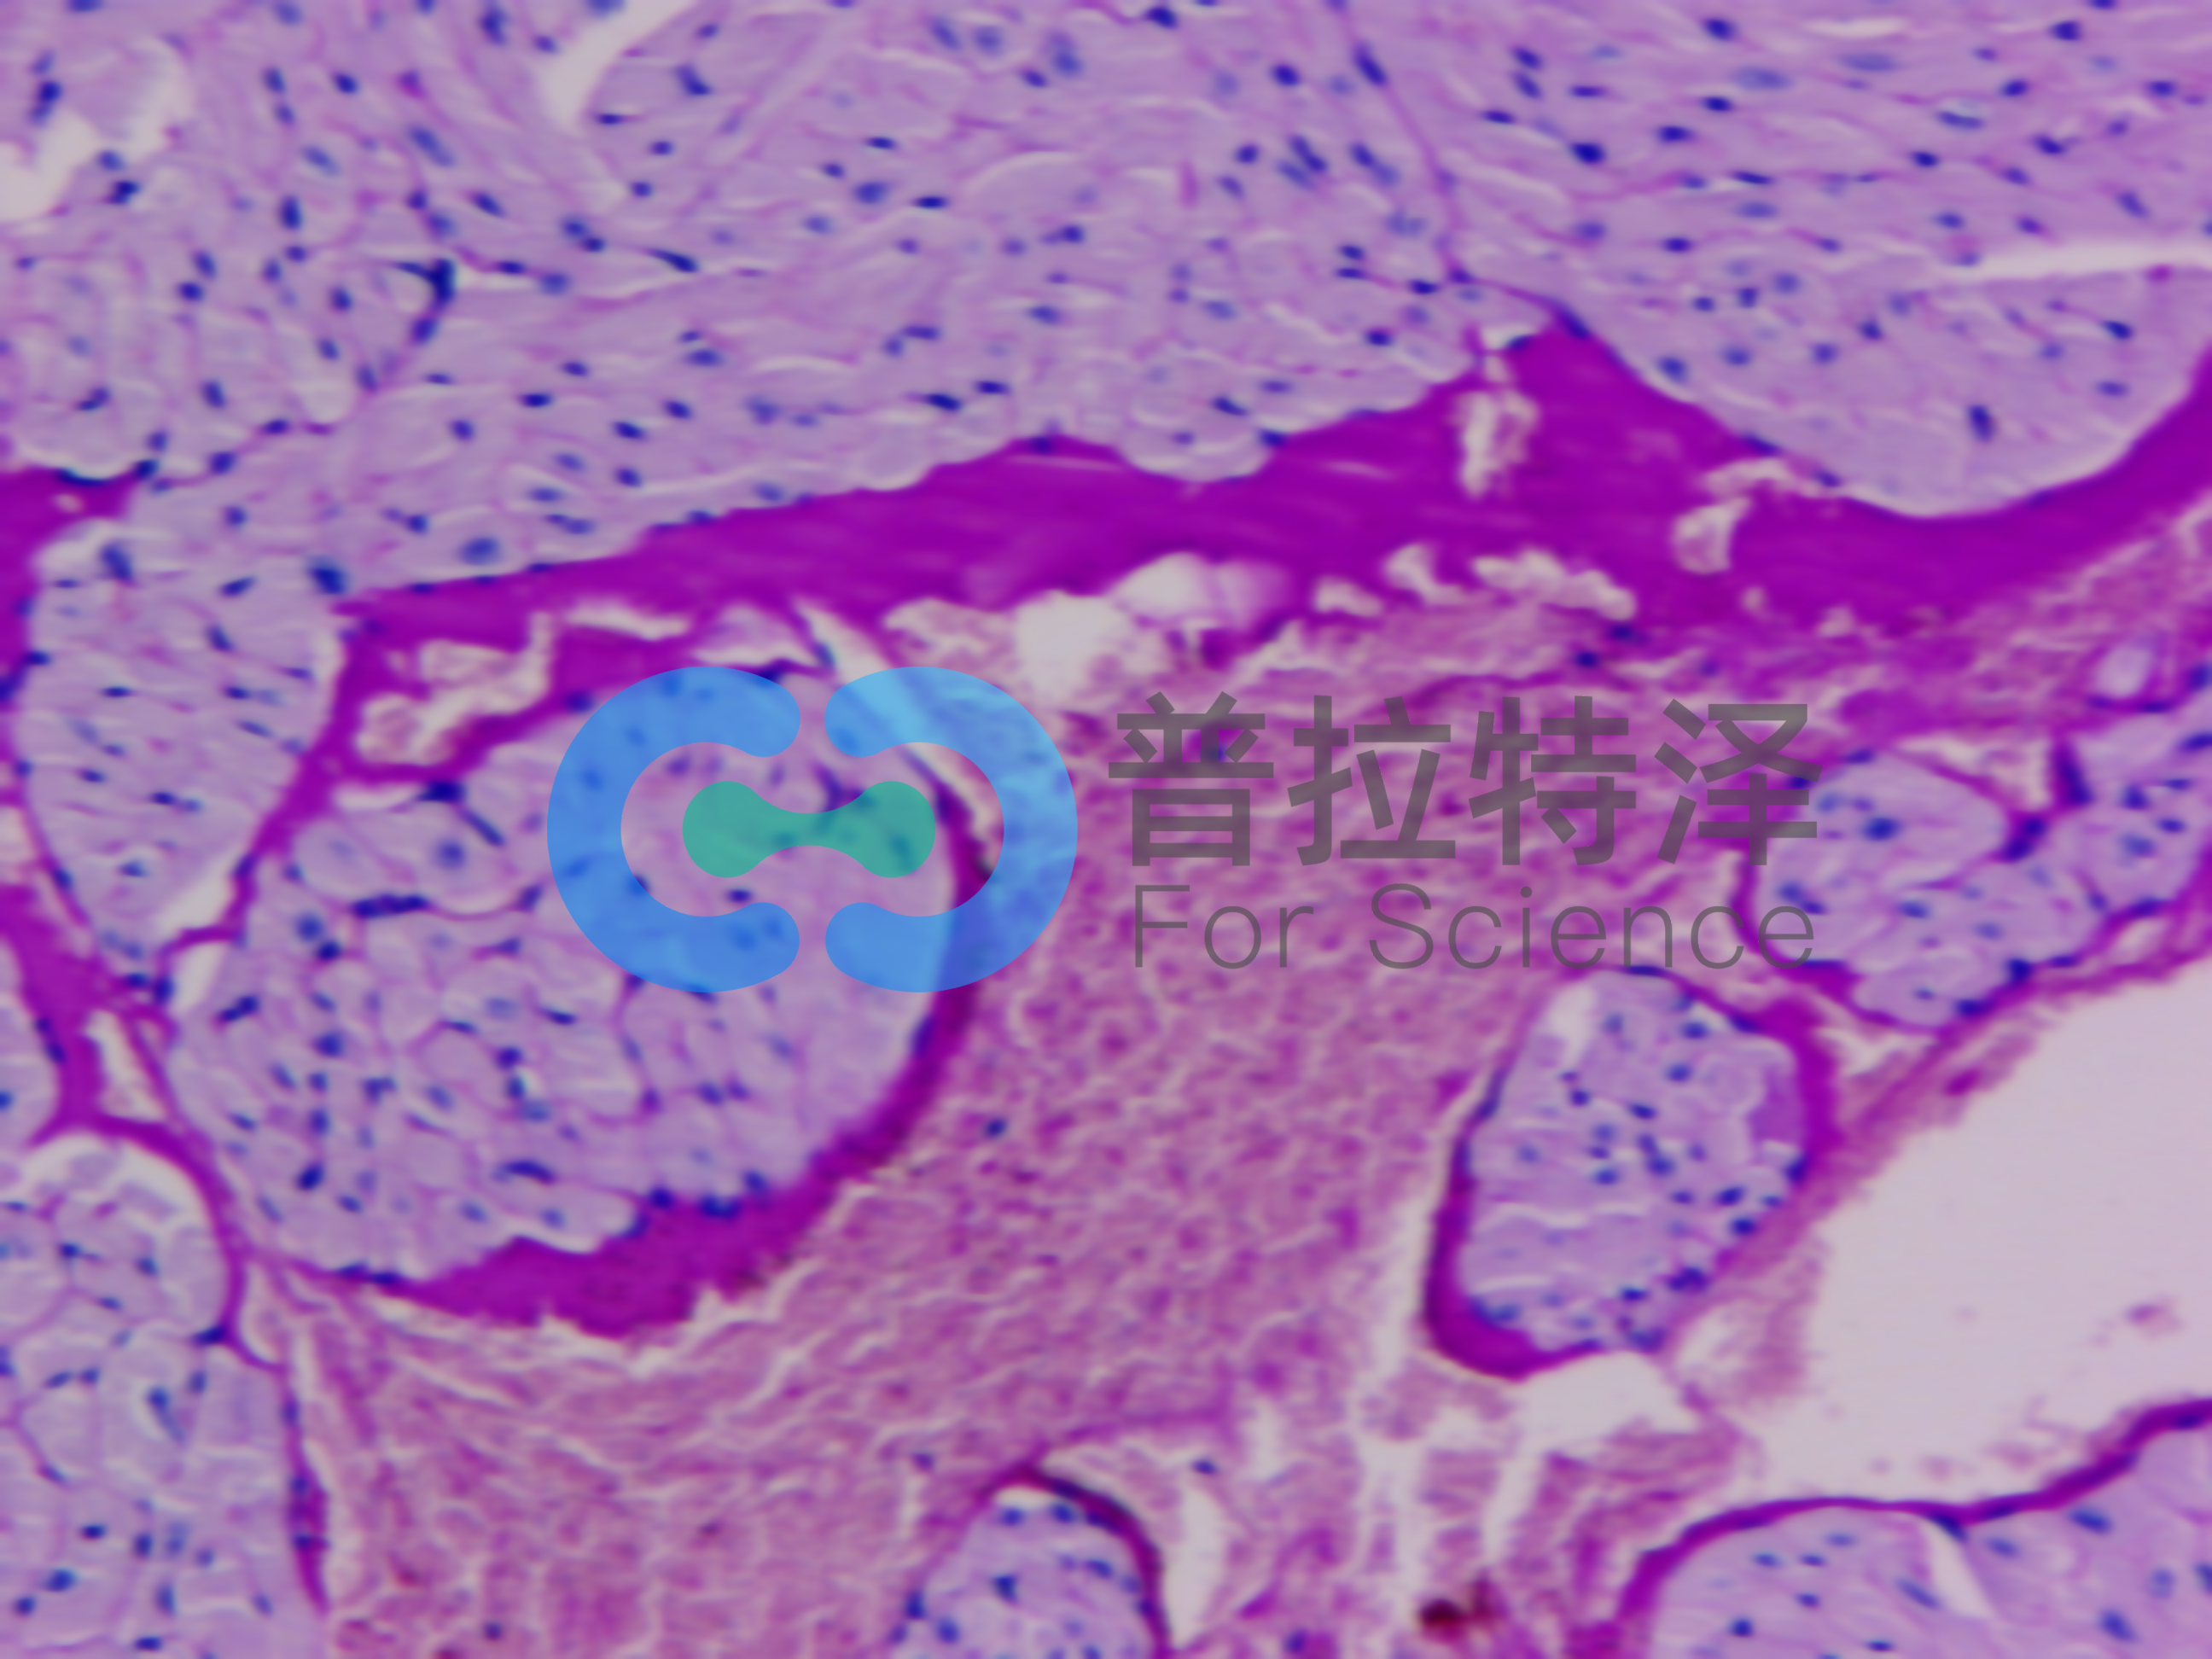

實(shí)驗(yàn)簡(jiǎn)介:PAS染色又稱過(guò)碘酸雪夫染色,糖原染色。一般用來(lái)顯示糖元和其它多糖物質(zhì)。

實(shí)驗(yàn)原理:糖原染色是病理學(xué)中常規(guī)的染色方法之一,氧化劑能氧化糖類及有關(guān)物質(zhì)中的1,2-乙二醇基,使之變?yōu)槎┡cSchiff試劑能結(jié)合成一種品紅化合物,產(chǎn)生紫紅色。PAS技術(shù)常用來(lái)顯示糖原和其他多糖,該染色液不僅能夠顯示糖原,還能顯示中性黏液性物質(zhì)和某些酸性物質(zhì),以及軟骨、垂體、霉菌、真菌、色素、淀粉樣物質(zhì)、基底膜等。

隨著醫(yī)學(xué)實(shí)驗(yàn)技術(shù)的發(fā)展,近年來(lái),糖原染色應(yīng)用的范圍更加廣泛,如用以證明與鑒別細(xì)胞內(nèi)空泡狀的性質(zhì),心肌病變及其他心血管疾病的診斷,糖原累積病診斷和研究,糖尿病的診斷和研究,用于某些腫瘤的診斷等。除用于糖原的鑒定和黏液的顯示外,還可以觀察腎小球基底膜、結(jié)腸杯狀細(xì)胞中性黏液物質(zhì)、阿米巴滋養(yǎng)體和霉菌的著色。為臨床診斷、分類和治療提供了重要的依據(jù)。